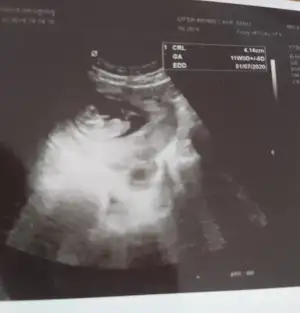

Ikra meyra Ikra meyra Buraya da paylaşabilirsiniz demişsiniz ☺️

• _20191212_123405.webp

_20191212_123405.webp

13,8 KB · Görüntüleme: 86

Ikra meyra Ikra meyra bu son gönderdiğim anlaşılabilecek gibi mi diğer uzaktan olan fotoğrafa net değil demiştiniz emin olmamakla beraber kız demiştiniz tekrar bakabilir misiniz zahmet olmazsa 💓

Hala net degil canım 12 hafta usg olursa paylaşırsınız. Bu usg kaç hafta 😊

Ikra meyra Ikra meyra canım burda 12+2 ultrasona göre. Tekrar gönder demiştin var mı acaba bi şansım bu sefer 😂